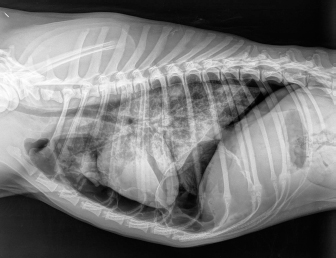

Case details for each of the five dogs included in the study are listed in Table 1. The etiology of the pneumothorax were congenital pulmonary bullae in two dogs, traumatic in one (road traffic accident), lungworm infection in one, and unknown in the remaining dog. Dog number 1 presented a large pulmonary bulla in the right cranial pulmonary lobe (Fig. 1). Dog number 2 presented four bullae: two in the medial aspect of the left cranial lung lobe (17 mm each), one in the caudal aspect of the left caudal lung lobe (26 mm), and another in the caudal border of the left caudal lung lobe (36 mm) (Fig. 2). Dog number 3 presented a large bulla measuring 33 mm in the medial aspect of the right middle lung lobe and around 10 blebs measuring from 3 to 6 mm in the ventral border of both right and left cranial lung lobes. Dog number 4 developed multiple small bullae and a larger one measuring over 10 cm, 24 hours after treatment of lungworm with spot on Imidacloprid and Moxidectin, which were responsible for a moderate unilateral pneumothorax (Fig. 3). Despite the severity of the pneumothorax, dog number 5 did not show any lesions on the computed tomography (CT) scan that could clearly explain its origin. Only one chest tube was placed in dogs 1, 2, 3, and 4. Two were placed in dog 5.

Fig. 1. CT transverse image of the thorax of the dog number 1 with pneumothorax showing a large pulmonary bulla in the right cranial lung lobe (arrow).